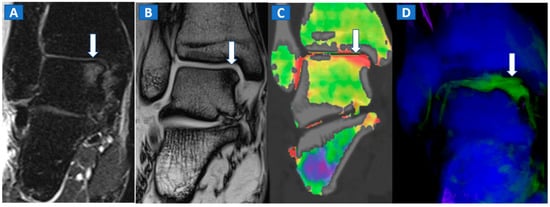

Figure 7.

A 44-year-old male with post-traumatic OCL of the talar dome. On the coronal STIR MRI image (A), a hyperintense subchondral area of BME is depicted on the medial aspect of the talar dome (arrow), which is consistent with the diagnosis of OCL of the talus. The lesion appears hypointense on the T1-weighted images ((B); arrow). On the 1 mm reconstructed 2D coronal DECT image (C) and coronal 3D DECT map, the lesion appears as a subchondral oedematous area (arrow), due to its increased water content. On the corresponding 3D image (D) the BME is coded in green (arrow).

DECT can also accurately depict BME in post-traumatic fractures of the knee (Figure 5). Specifically, DECT can identify BME associated with ligamentous injuries following indirect trauma [6,15]. Moreover, additional color-coding can be used to better delineate meniscal tears (Figure 6). OCL, of the knee or ankle, are usually apparent from a markedly oedematous subchondral region (such as femoral condyle or astragalic dome), surrounded by a more subtle BME (Figure 7). With the availability of isotropic high-resolution CT images, it is possible to rule out migrated fragments and to confirm the integrity of the cortical bone.

Typically, the talus is the site most often involved in post-traumatic BME of the ankle. Subchondral bone sclerosis and thick cortical bone in the midfoot area may present significant limitations here [16].